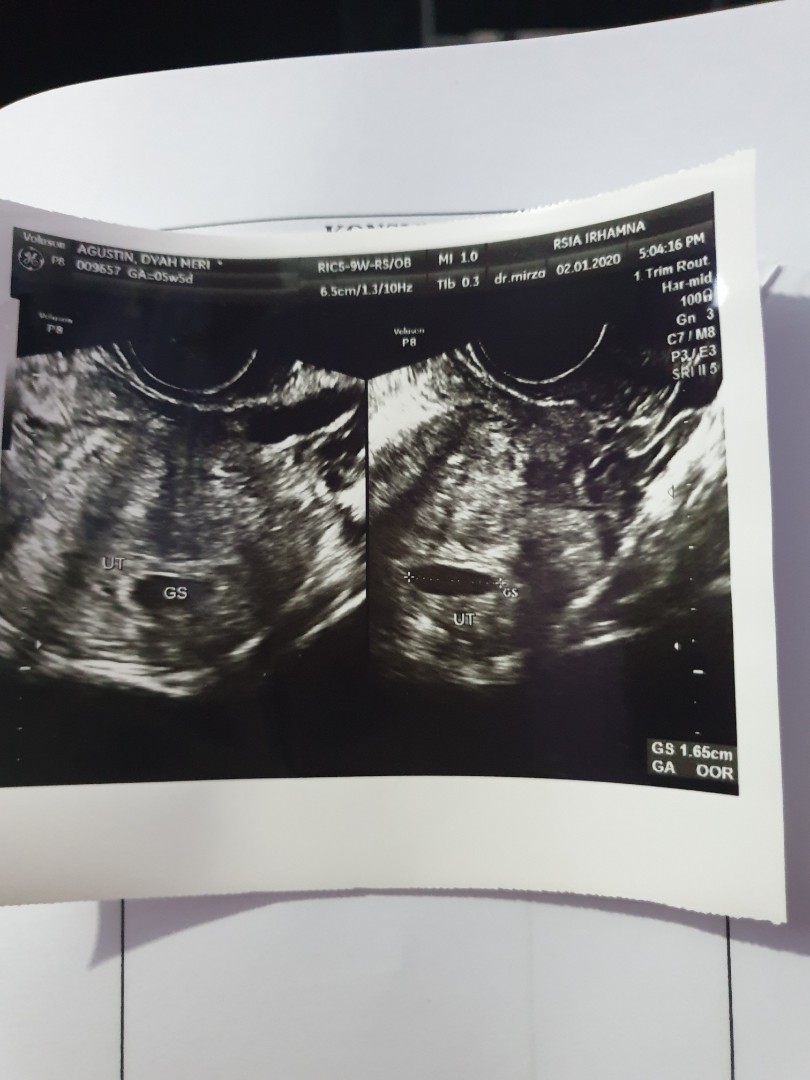

Ada yg pernah gak? Klo dihitung dri hpht misalkan usia kehamilannya 5minggu 6hari tpi pas usg masih 5minggu 4 hari kayak gtu,beda duahari? Ini hasil usg aku brusan, kata dokternya sih bru kantong doang yg kelihatan,jdi dsuruh blik lagi 2 minggu kemudian, ada yg pernah usg 5 minggu dh kelihatan janinnya?